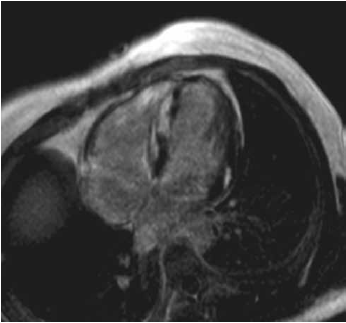

Se solicitó una resonancia magnética nuclear (RMN) cardíaca que mostró hallazgos compatibles con enfermedad infiltrativa, observándose edema miocárdico difuso, que luego del realce tardío con la inyección de gadolinio evidenció áreas de fibrosis focal abarcando segmentos subepicárdicos, intramiocárdicos y suben-docárdico (Figuras 3 y 4).